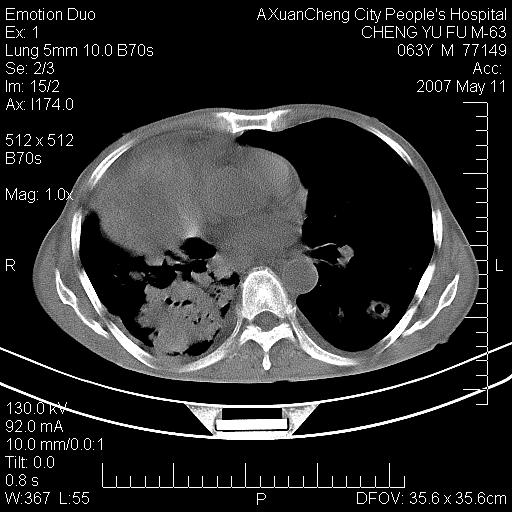

以下是引用小初学者在2007-5-11 19:32:00的发言:[br]1、首先考虑干酪性肺炎支气管播散[br]2、支气管肺泡癌待排

以下是引用zhangzhongshou在2007-5-11 19:30:00的发言:[br]细支气管肺泡癌可能性大。